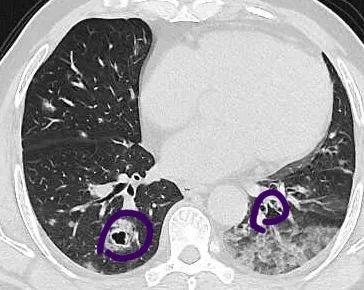

2020年5月左右 , 一向身体很好的张伯却无缘无故出现了咳血症状 , 当地医院肺部CT检查结果显示 , 他双肺布满了圈状的病灶 , 看过去就像是一个个白色的圆圈 , 大小不一 , 最大的有手镯那么大 , 共计有七八个 。

紫色圈里均为病灶

“这是非常少见的肺炎样肺癌 , 一般来说 , 肿瘤病灶都是实心 , 就算形态不一 , 都较容易判断 。 但这位患者的腺癌肿瘤细胞有分泌粘液的功能 , 分泌出的粘液将肿瘤包裹起来了 , 就在影像学上呈现出圈状 。 一般这种分泌型肿瘤常见于消化道 , 肺部非常少见 , 很多医师可能都没遇到过 , 容易错认为肺炎 。 ”医生说 。